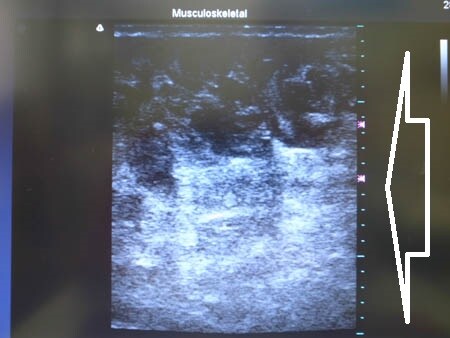

右横からも状態を比較してみましょう。

↓ ↓ ↓

左横からも。

術前、術直後の劇的変化。

根こそぎ竹田先生ならでは!

のものだと自負しています。

圧倒的吸引量で圧倒的満足度。